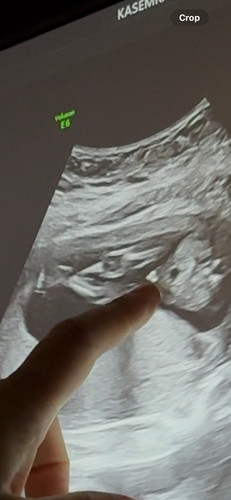

สอบถามค่ะ แบบนี้มีโอกาสได้ลูกชายไหมคะ

15+5 week เจอแบบในรูปค่ะ ลุ้นมาก ##ขอบคุณสำหรับคอมเม้นล่วงหน้าค่ะ #ตั้งครรภ์

ซาวด์รอบหน้า น่าจะชัดกว่านี้นะคะ ใกล้ได้รู้เพศน้องแล้วนะคะ ขอให้สมหวังนะคะ

น่าจะจู๋นะคะแม่ รออีกนิดจะชัดกว่านี้ค่ะ

อาจเป็นไข่น้องนะคะ555

น่าจะได้ค่าแม่

มีโอกาสค่ะ

หมอว่าไงค่ะ

หมอบอกมีโอกาสได้ ช ค่ะ แต่อาจจะยังเล็ก